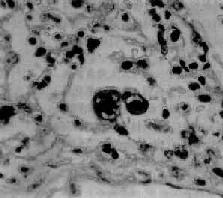

腺病毒肺炎

图9-21 腺病毒肺炎

图中央可见肿大肺泡上皮细胞中的核内包含体

早期或轻型病毒性肺炎表现为间质性肺炎,炎症从支气管、细支气管开始,沿肺间质发展,支气管、细支气管壁及其周围、小叶间隔以及肺泡壁等肺间质充血、水肿,有一些淋巴细胞和单核细胞浸润,肺泡壁明显增宽(图9-20)。肺泡腔内一般无渗出物或仅有少量浆液。病变较重者,肺泡也可受累,出现由浆液、少量纤维蛋白、红细胞及巨噬细胞组成的炎性渗出物,甚至可发生组织坏死。有些病毒性肺炎(如流感病毒肺炎,麻疹病毒肺炎、腺病毒肺炎等)肺泡腔内渗出较明显,渗出物浓缩凝结成一层红染的膜样物贴附于肺泡内表面,即透明膜形成。支气管上皮的肺泡上皮也可增生,甚至形成多核巨细胞。麻疹病毒肺炎的病变特点为在间质性肺炎的基础上,肺泡壁上有透明膜形成,并有较多的多核巨细胞(巨细胞肺炎),在增生的上皮细胞和多核巨细胞的胞浆内和胞核内可检见病毒包含体。病毒包含体常呈球形,约红细胞大小,呈嗜酸性染色,均质或细颗粒状,其周围常有一清晰的透明晕。其他一些病毒性肺炎也可在增生的支气管上皮、支气管粘液腺上皮或肺泡上皮细胞内检见病毒包含体。如腺病毒肺炎可在增生的上皮细胞核内(图9-21),呼吸道合胞病毒肺炎可在增生的上皮细胞胞浆内,巨细胞病毒肺炎也可在增生的上皮细胞核内检见病毒包含体。检见包含体是病理组织学诊断病毒性肺炎的重要依据。